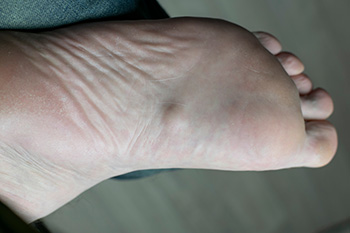

Understanding Plantar Fibromatosis

Understanding Plantar FibromatosisPlantar fibromatosis is a condition where benign, firm nodules develop in the plantar fascia, the thick band of tissue along the bottom of the foot. These nodules are typically slow-growing and non-cancerous but can cause discomfort...